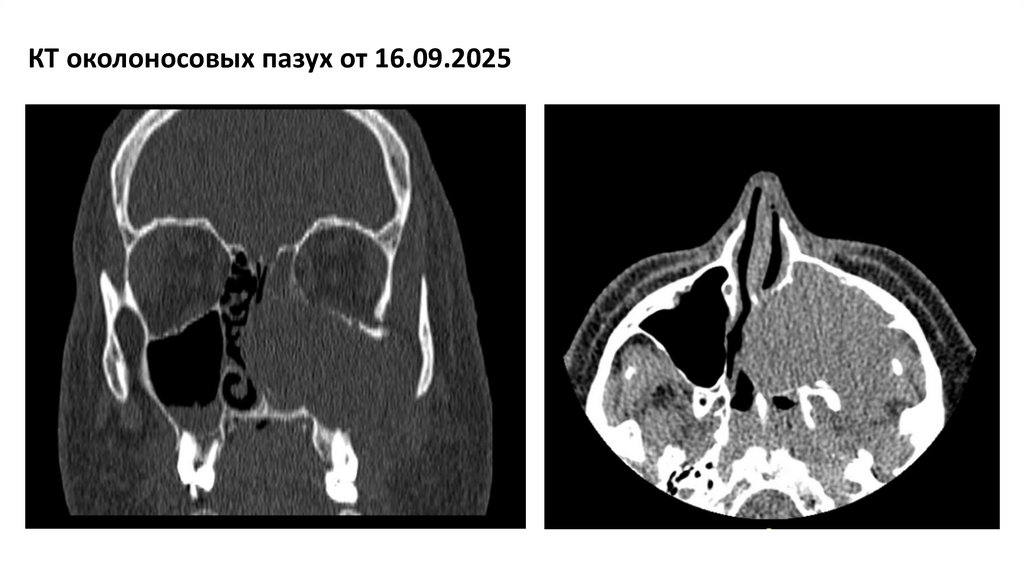

КТ околоносовых пазух от 16.09.2025

На серии компьютерных томограмм околоносовых пазух, выполненных по специальной программе, определяется:

В левой верхнечелюстной пазухе отмечается объемное образование мягкотканной плотности, неоднородной структуры за счет гиперденсных включений,

тотально заполняющее верхнечелюстную пазуху слева, с деструкцией прилежащих костных структур:

-медиальная, верхняя, нижнелатеральная стенки верхнечелюстной пазухи слева

-передняя стенка верхнечелюстной пазухи

-клеток решетчатого лабиринта слева

-костные структуры носовых раковин

- костные структуры перегородки носа

-медиальной стенки глазницы?

-передней стенки основной пазухи

-передней стенки сонного канала

-альвеолярного отростка верхней челюсти

Определяется выход мягкотканного компонента с распространением в полости носовых ходов слева, носоглотку, подкожно-жировую клетчатку слева,

крыловидно-небную и подвисочную ямки слева.

Пневматизация правой верхнечелюстной, основной, лобной пазух сохранена. Ячейки решетчатого лабиринта справа нормально контурируются, костные

стенки не изменены, пневматизация сохранена. Остиомеатальное соустье справа проходимо.

По нижней стенке правой верхнечелюстной пазухи отмечается гиперплазия слизистой толщиной до 6мм, в правой верхнечелюстной пазухе отмечается

гиподенсное образование, округлой формы широким основание, прилежащее к передней стенке размерами до 19х12мм (киста).